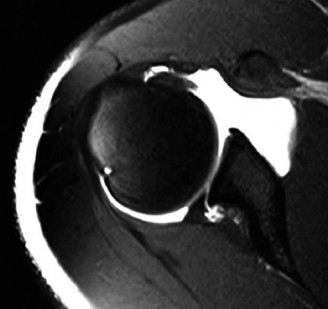

Advanced Cross Sectional Imaging

Given the clinical suspicion for a capsulolabral injury, Magnetic Resonance Arthrogram is the gold standard diagnostic modality and was subsequently ordered. The intra articular gadolinium distends the joint capsule, allowing for superior visualization of labral pathology.

The axial T1 fat saturated images demonstrate contrast imbibition between the posterior labrum and the glenoid articular cartilage, extending from the 7 o clock to the 10 o clock position, diagnostic of a posterior labral tear. There is associated stripping of the posterior capsule, consistent with a posterior labrocapsular periosteal sleeve avulsion lesion.

Furthermore, the sagittal oblique and coronal images reveal a patulous posterior capsule, indicative of capsular redundancy secondary to repetitive microtrauma. Evaluation of the spinoglenoid notch shows no evidence of a paralabral cyst, and the muscle bellies of the rotator cuff demonstrate no fatty infiltration or atrophy. The anterior labrum and the long head of the biceps tendon anchor appear intact.